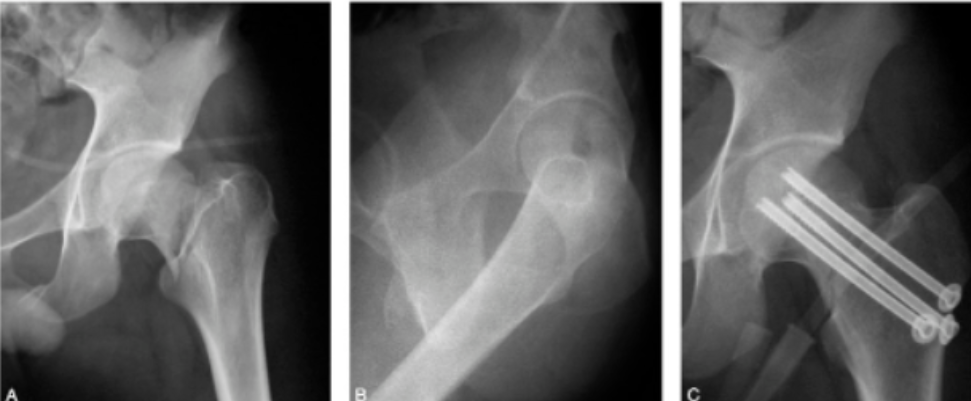

股骨颈骨折内固定治疗的手术技巧,一篇总结到位!